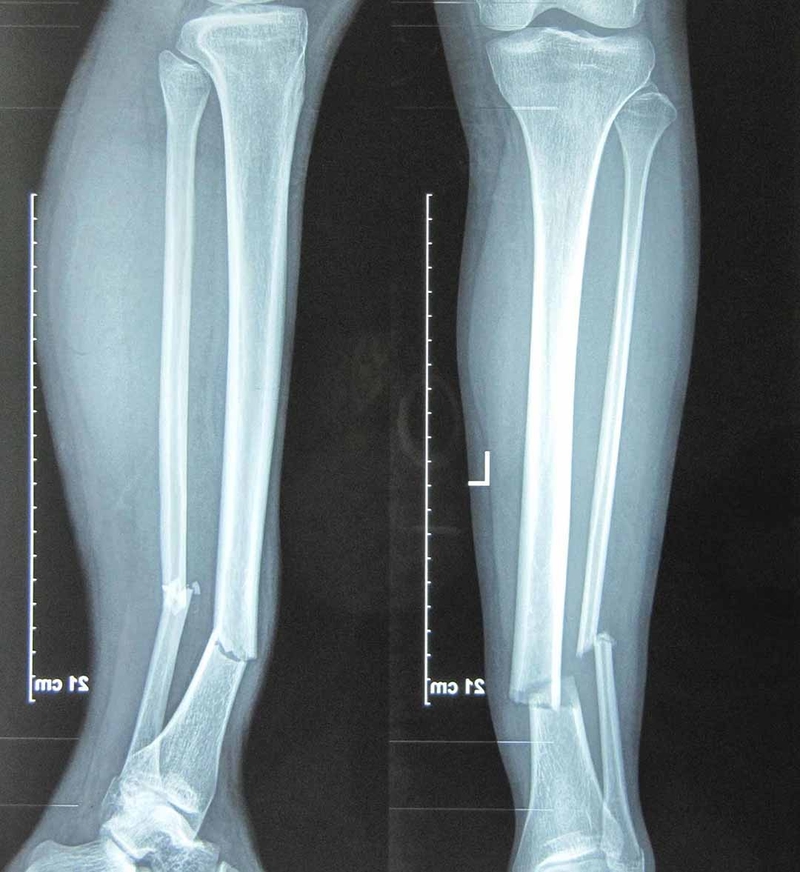

Gãy chân là tình trạng gãy xương đùi hoặc hai xương cẳng chân. Xương đùi là xương lớn và dài nhất cơ thể, chính vì thế gãy xương đùi là chấn thương nặng nguy hiểm đến tính mạng, lượng máu mất rất lớn nguy cơ sốc mất máu. Gãy hai xương cẳng chân là loại gãy xương phổ biến, tuy nhiên rất khó trong việc điều trị và để lại nhiều biến chứng sau này. Bởi vậy, thực hiện tốt các bước sơ cứu gãy chân ban đầu chính là góp phần thành công trong điều trị cho bệnh nhân.

Gãy chân chia thành 2 dạng là gãy kín và gãy hở. Gãy xương kín là tình trạng gãy xương nhưng không có vết thương hở hoặc chảy máu biểu hiện bên ngoài da, vì vậy có thể bỏ sót tổn thương.

Hướng dẫn sơ cứu gãy chân đúng cách 1 Gãy chân ở các vị trí khác nhau biểu hiện khác nhau và tiên lượng cũng khác nhau

Gãy chân hở là khi ổ gãy thông với môi trường bên ngoài. Có thể thấy đầu xương gãy lộ ra bên ngoài và chảy rất nhiều máu. Hậu quả gãy xương hở thường nặng nề hơn gãy kín.